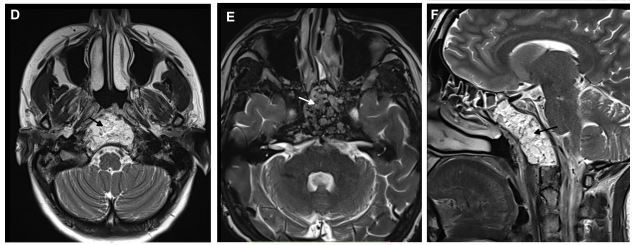

术前轴位D、E和矢状位FT2加权MRI显示斜坡脊索瘤延伸至岩尖、海绵窦、蝶窦(SS)及咽后空间。

术后轴位D、E和矢状位F T2加权MRI显示肿瘤切除,保留了双侧鼻窦的解剖完整性,并在缝合前使用脂肪进行闭合。